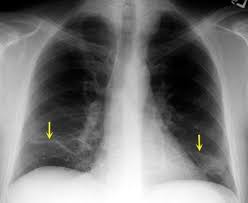

أعراض استرواح الصدر.. يعاني بعض الأشخاص من مشكلة استرواح الصدر الذي يعرف أيضًا بانخماص الرئة، وعادة ما تظهر حالة استرواح الصدر عند تسرب الهواء إلى المساحة بين الرئة وجدار الصدر، فيضغط هذا الهواء على الجهة الخارجية للرئة، ما يعرضها للانقباض والانهيار، وقد يكون استرواح الصدر انقباضًا كاملًا للرئة أو انقباضًا لجزء منها فقط، فهيا نتعرف فيما يلي على أعراض استرواح الصدر.

أعراض استرواح الصدر

وعن أعراض استرواح الصدر، فحسبما ورد بموقع"مايو كلينيك" الطبي هناك عدة أعراض وعلامات تشير للإصابة باسترواح الصدر والتي عادة ما تتضمن ما يلي:

- الشعور بألم مفاجئ في الصدر.

- مع الإحساس بضيق في النفس.

جدير بالذكر أن شدة أعراض استرواح الصدر عادة ما تتوف على حجم الانخماص الذي تتعرض له الرئة، إذ قد يكون انخماص الرئة لدى بعض الحالات من الأمراض التي تهدد الحياة.